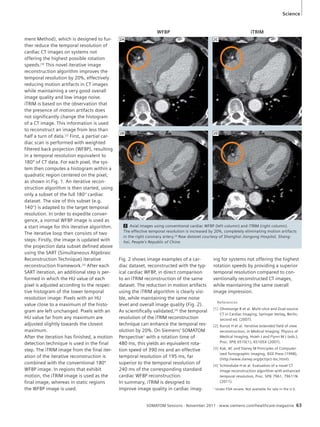

window: note

motion-free

delineation of

the diaphragm,

pulmonary

vessels and

infarction in

the left upper

lobe, although

the patient

was breathing.